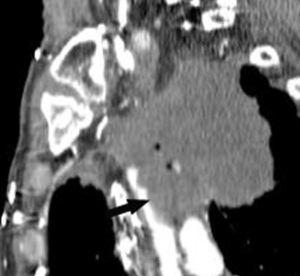

La diferenciación entre tumores T3 y T4 puede ser difícil empleando sólo técnicas de imagen. Cuando se evidencia destrucción ósea (costal o vertebral), existe masa en el espacio intercostal (fig. 3), o las estructuras mediastínicas están claramente englobadas por el tumor, el diagnóstico es obvio (fig. 2). Sin embargo, sin estos hallazgos, la predicción de invasión es mucho menos fiable. Se han descrito diferentes signos que pueden ayudar a determinar la invasión de pared torácica. Éstos incluyen el contacto con la superficie pleural mayor de 3 cm, el engrosamiento pleural, la ausencia de plano graso y la presencia de un ángulo obtuso entre el tumor y la pared torácica. Aplicando al menos dos de estos criterios la sensibilidad es de un 87%, sin embargo la especificidad es baja (59%)4. El dolor torácico localizado es un síntoma importante que a menudo está asociado a invasión de pared.

Fig. 3.--Invasión de pared torácica. Tomografía computarizada (TC) torácica con contraste. Reconstrucción coronal con ventana de hueso (A) y de volumen (B). La presencia de destrucción ósea (flecha negra) o de masa en el espacio intercostal (flecha), son los únicos signos fiables de infiltración de la pared torácica.